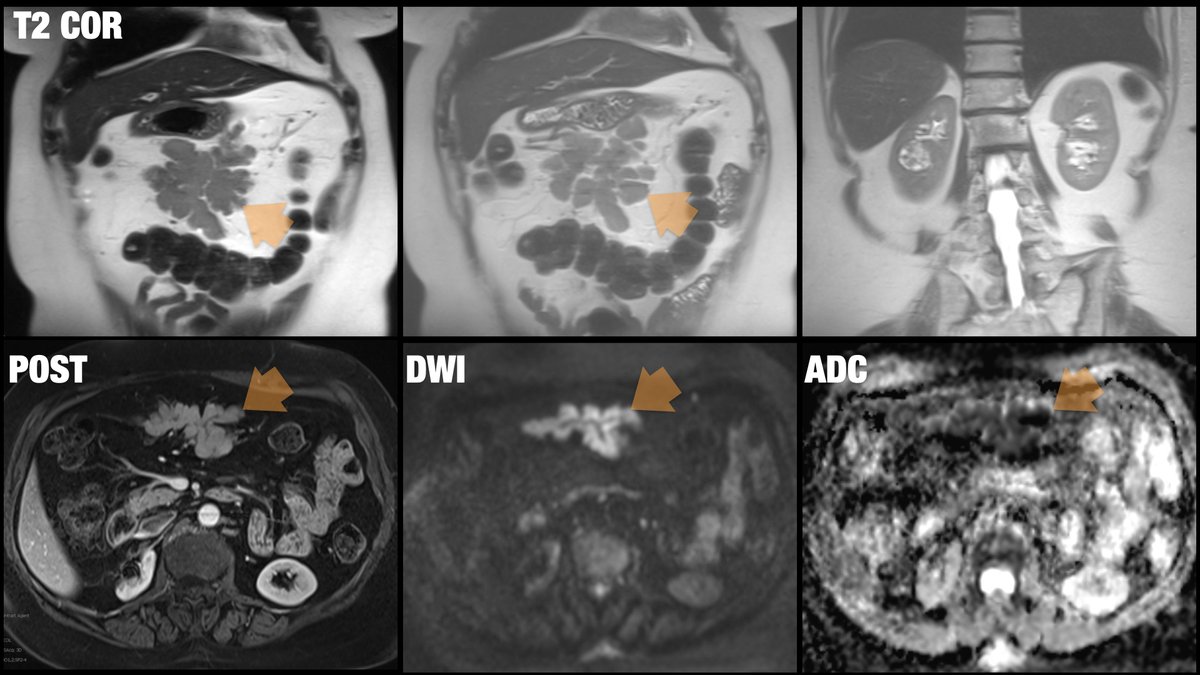

57-year-old female patient presenting with soft tissue mass in the mesentery... If an image is worth a thousand words... you don't need the history on this one! Diagnosis? Next step? @BrighamRad @FOAMrad @SAR_RFS @futureradres @ARRS_Radiology @Abdominal_Rad @CBRadiologia

All right, all right... Where is the spleen? This patient is status post splenectomy for trauma. MRI performed 5 years later confirming benign vs indolent etiology... this is... Mesenteric SPLENOSIS! @BrighamRad @FOAMrad @SAR_RFS @futureradres @ARRS_Radiology @Abdominal_Rad

Thanks everyone... I feel better now... In my humble opinion, this case had lymphoma written all over the upper abdomen! I went further and suggested high-grade diffuse large B-cell lymphoma as the most likely diagnosis! However, biopsy showed metastatic melanoma! (and I lost a